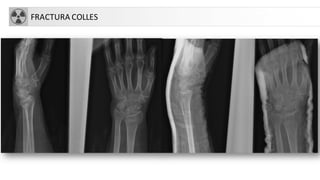

• FX Colles. Criterio: fractura de extremo distal de radio con

angulación dorsal y acortamiento radial, que produce la

típica deformidad en dorso de tenedor

FRACTURA COLLES